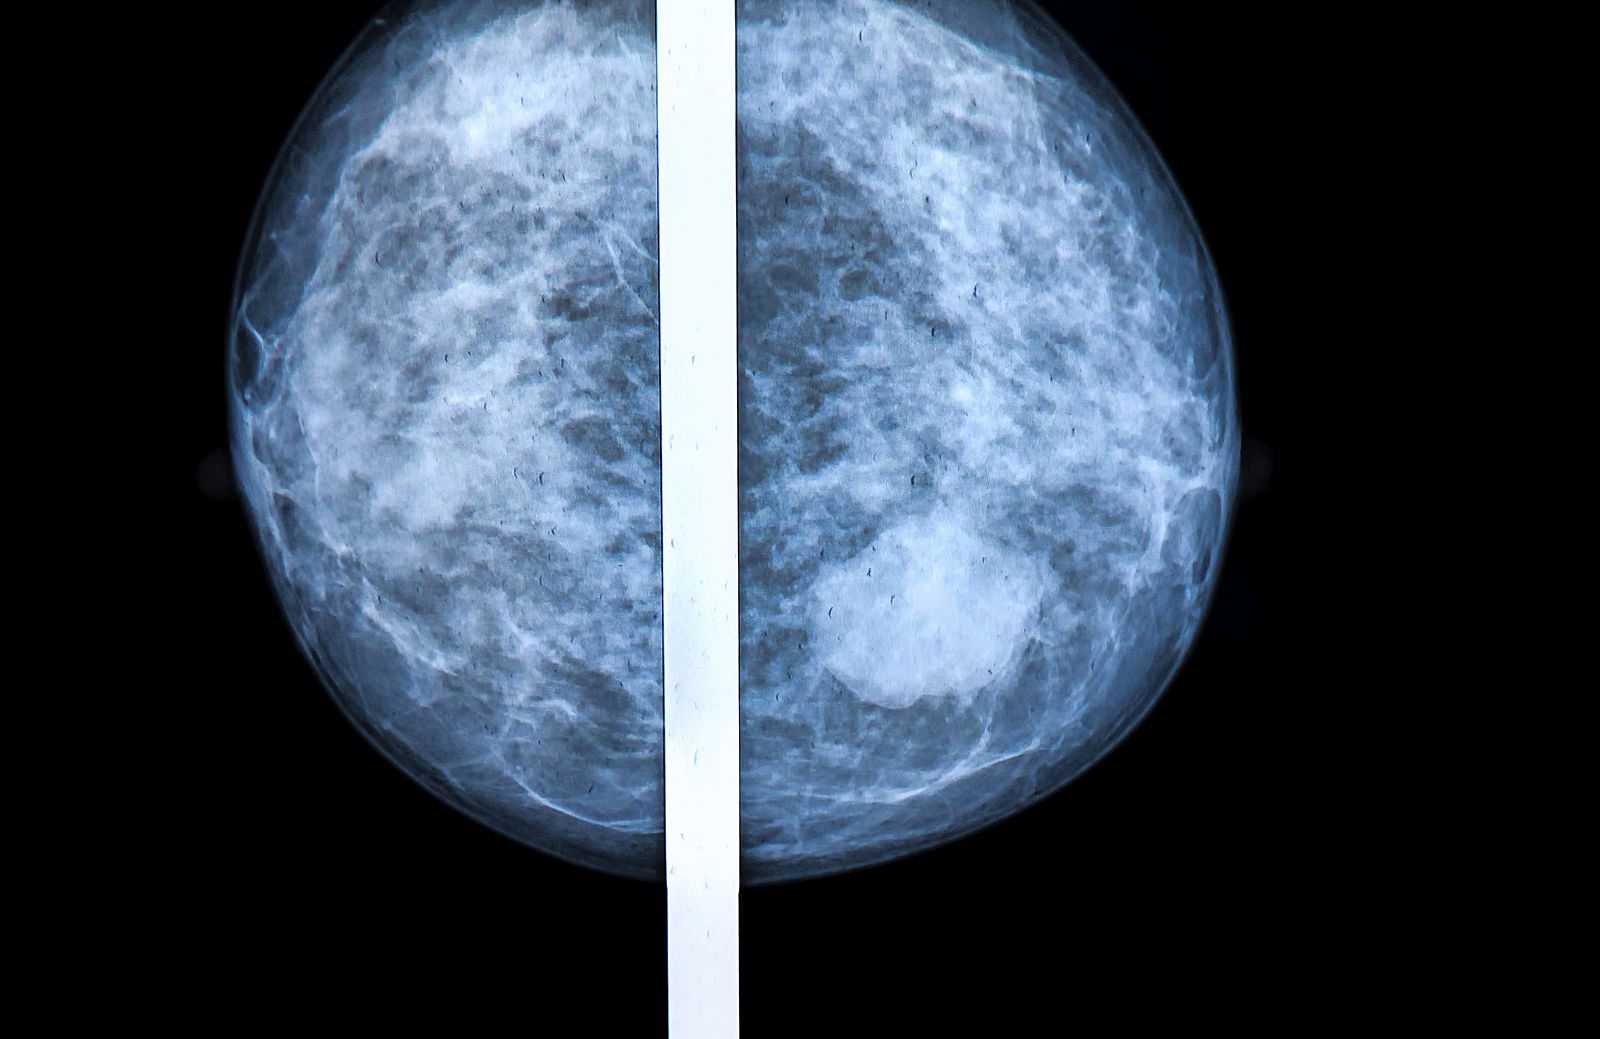

Imagen de una mamografía.